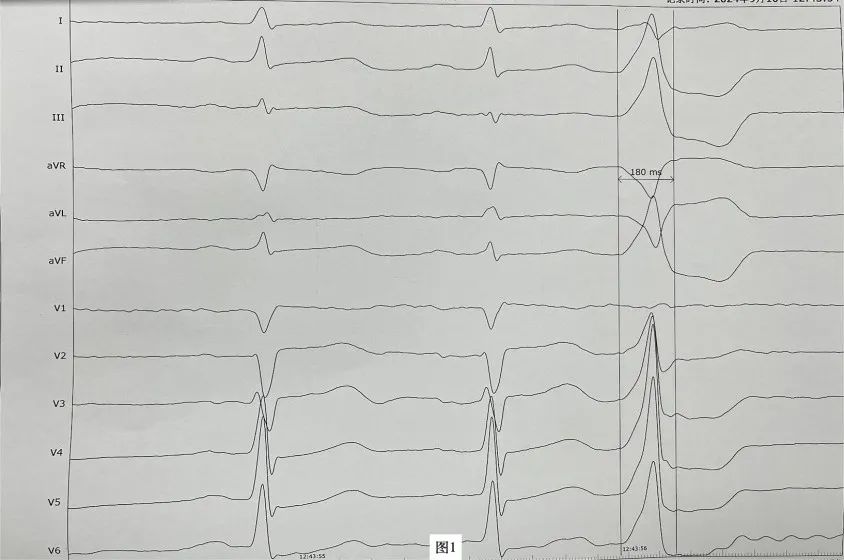

李先生(化名),近年来一直受病痛折磨,反复心悸、胸闷发作,夜间难以入睡,多次在外院就医治疗效果均不理想。近日,李先生再次因心悸症状明显慕名来到亚洲色吧 附二院心血管内科二病区周明礼门诊就诊。患者心电图检查提示有室性早搏,24小时动态心电图提示室早超过40000次,占总心跳40%左右。经诊断,患者有频发室性早搏,心悸症状因室早所致。周明礼认真分析病情后,告诉患者这个病不用开刀,在清醒状态下,从腿部穿刺血管将消融导管送入心脏进行心脏射频消融治疗就可以得到根治,并且术后第二天就可以下床走路。但因该患者早搏起源左室summit区域(图1),位置刁钻,难度较大,能够成功手术的医院屈指可数。亚洲色吧 附二院心血管内科二病区开展射频消融手术多年,该区域室性早搏消融成功率较高,受疾病困扰多年的患者听到这个消息很高兴,并表示辗转就医多年终于看到了希望,决定在医院进行手术治疗。